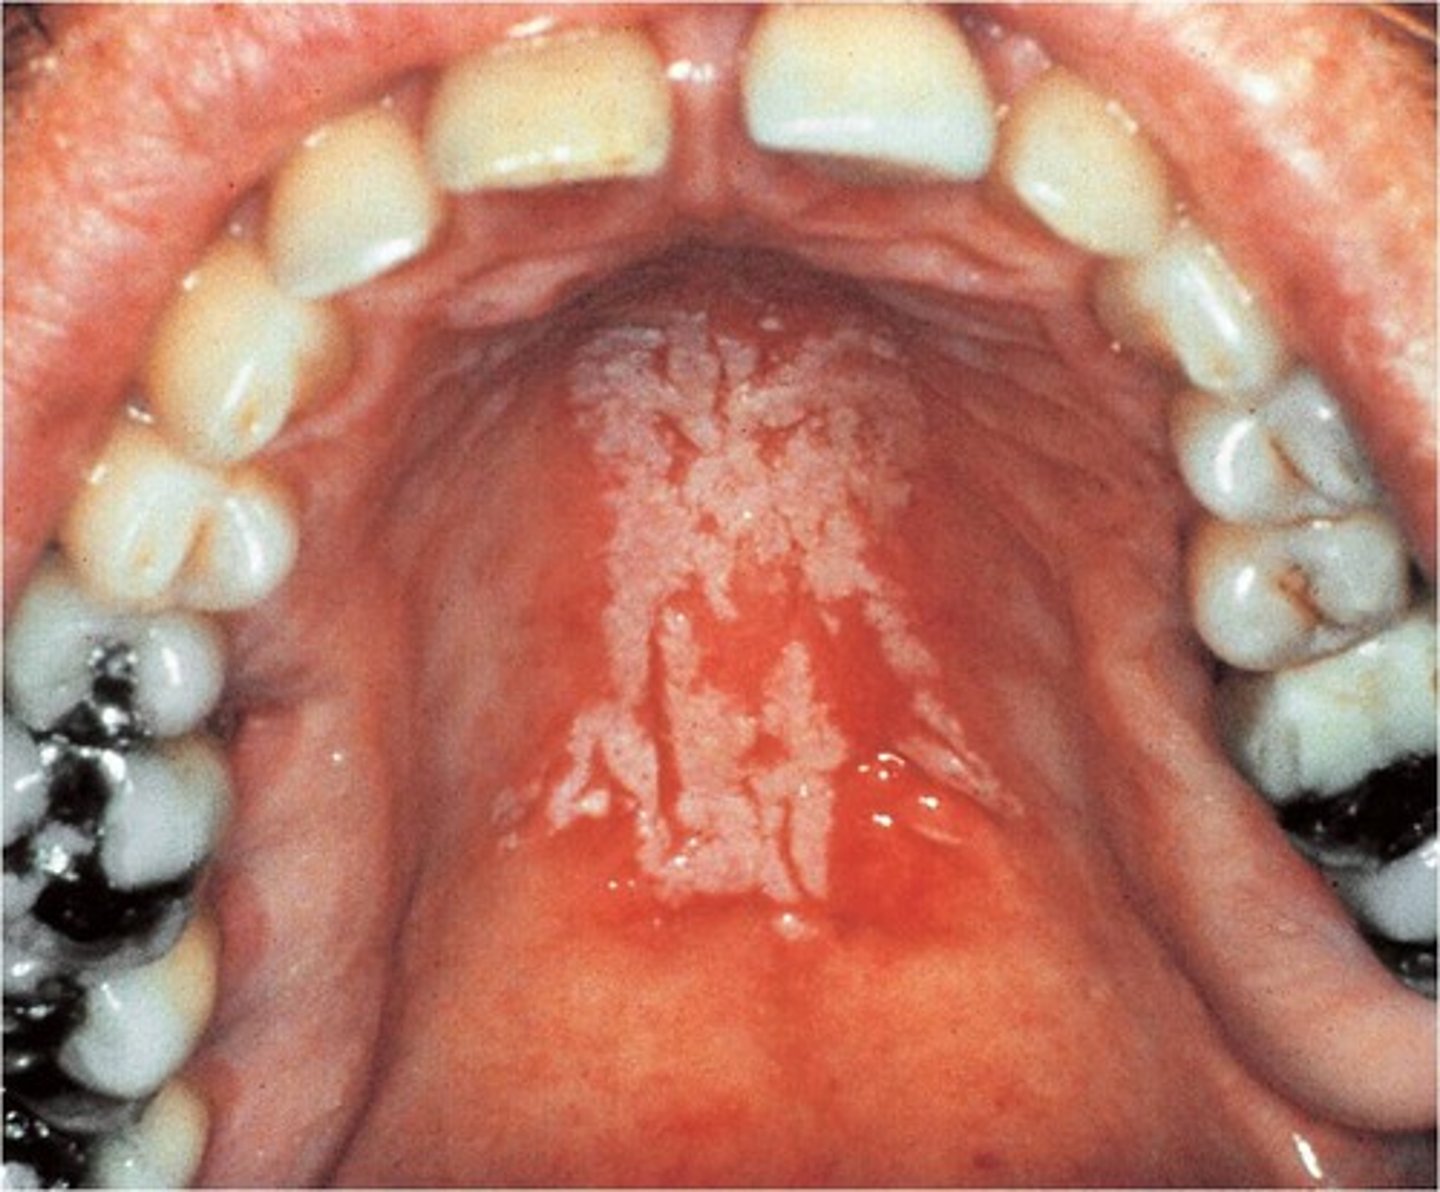

Candidiasis

Infection of the skin mouth (also called thrush) or vagina caused by the yeast type fungus candida albicans. candidiasis normally present in the mucous membranes, overgrowth causes an infection. esophagus candida they cyst is often seen in patients with AIDS (acquired immunodeficiency syndrome)